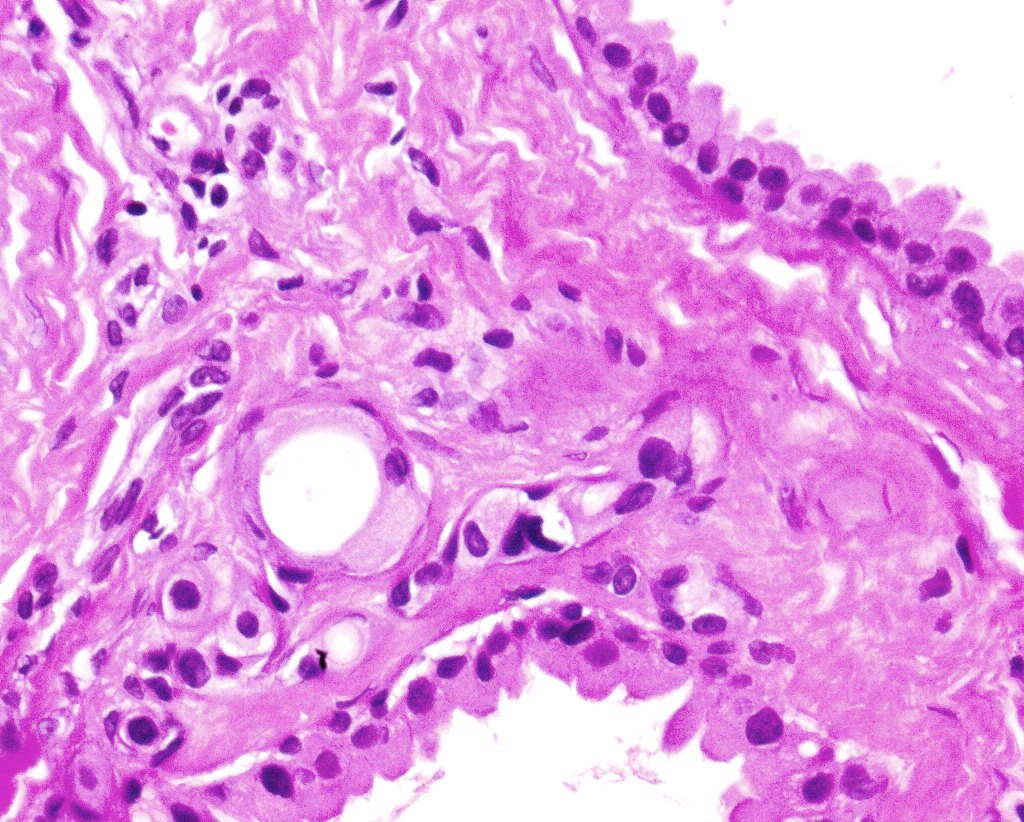

Histological features

•Outer myoepithelial cells & inner layer of columnar cells with eosinophilic cytoplasm showing decapitation secretion

•DPAS +ve intracytoplasmic granules